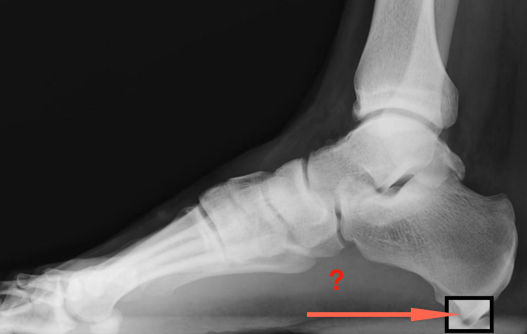

Anatomiquement, s’agit-il de ceci ? (qui devrait faire mal)

Ou de ceci ? (qui devrait faire mal)

Eh bien non, il s’agit de ceci ! Et qui ne « pique » pas…

Qu’en est-il de cette fameuse épine qui ne pique pas ? L’épine de Lenoir est une trouvaille radiologique. Elle se situe à l’origine de l’insertion des courts fléchisseurs des orteils. Elle est observable chez 50 % des cas de fasciite plantaire et chez 15 % de la population asymptomatique. Elle n’entraîne pas de douleur en soi et il n’y a pas de lien précis entre l’épine et la fasciite (aponévrosite plantaire).